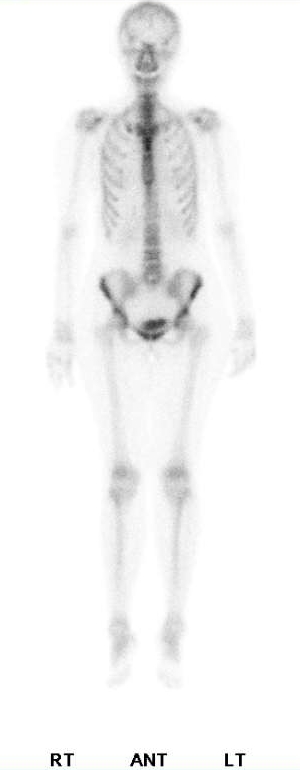

這是一位30多歲的肺癌女性患者,在連續的bone scan追蹤系列影像,由於是肺癌患者,所以大家的焦點都集中在肺部,可是在中間的那一次檢查裡,我們的醫生突然發現病人右邊的股骨頸那邊好像出現了甜甜圈的影像,該不會是治療的藥物造成了那邊的缺血性壞死AVN?於是就在報告上提到了這件事,然後臨床的醫師也很關心這個情形,就安排了核磁共振,結果卻是正常,接著病人又來進行第3次的bone scan追蹤,這次原先懷疑是AVN的地方竟然就沒事了,我跟我們家的醫師反反覆覆的看了幾次影像的原始檔,最後得出的結論是,第2次的影像有可能是口袋裡有銅板,造成的影像缺損才會那麼的圓,但是由於當時也沒有補局部的影像,因此一切也都是猜測。這件事告訴我們,首先,就算是已經確定病情的患者,在判讀影像時也要多留意其他的區域,才不至於有遺漏的地方,再者,就算病人說身上都沒有金屬或是其他異物,也不代表你可以放心的照,看到怪怪的地方,還是多檢查一遍會比較好。

![]() |

2018/7/23 |

2018/10/19 |

2019/1/14 |